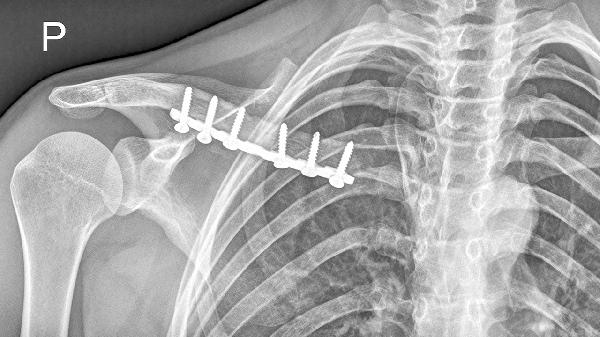

锁骨骨折多数情况下无需手术治疗。治疗方案选择主要取决于骨折类型、移位程度、患者年龄等因素,保守治疗方式包括八字绷带固定、锁骨带固定、限制活动、物理治疗及药物镇痛。

无移位或轻度移位的锁骨中段骨折通常选择保守治疗。这类骨折稳定性较好,通过外固定可达到自然愈合,愈合周期约6-8周。若为粉碎性骨折或伴有血管神经损伤,则需手术干预。

骨折端重叠小于2厘米或成角小于30度时优先考虑非手术治疗。严重移位可能导致畸形愈合影响肩关节功能,此时需手术复位内固定。儿童锁骨骨折因骨膜较厚,即使明显移位也多可保守治疗。